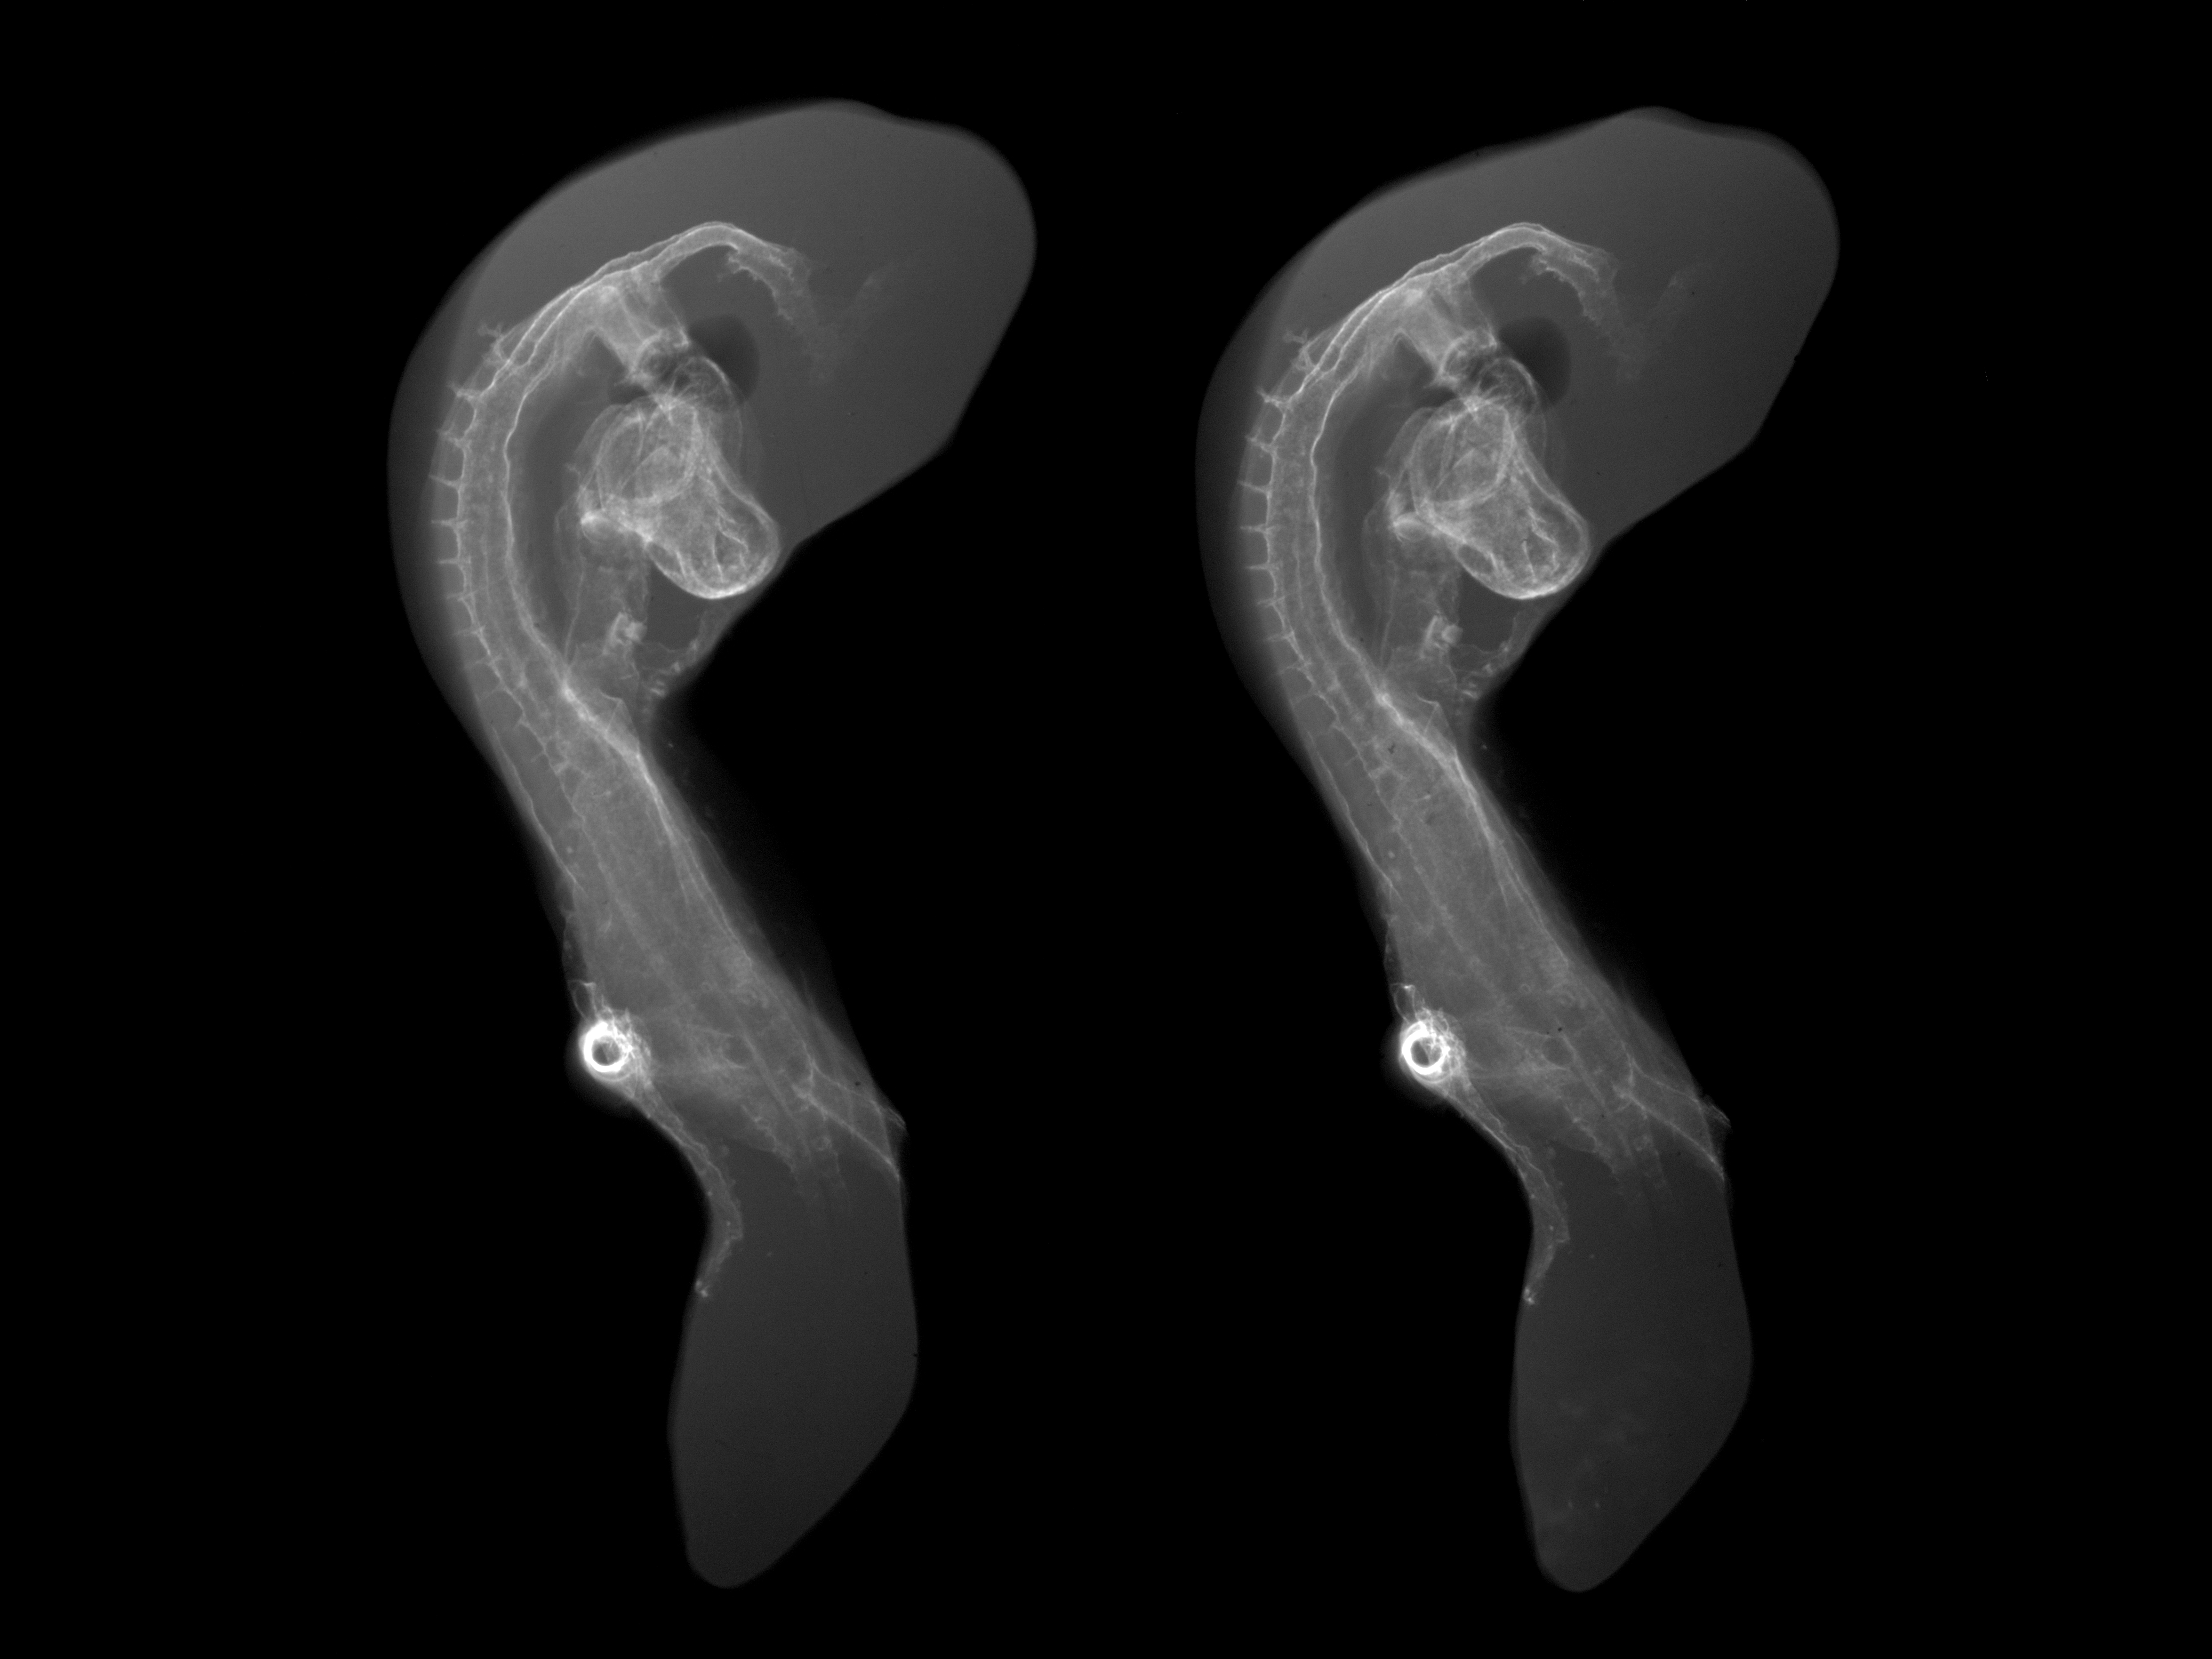

Chick Embryo Microangiography

Hamburger-Hamilton (HH) Stage 16 (approx. 2.1 - 2.5 days)

Stereo X-Ray Micrographs